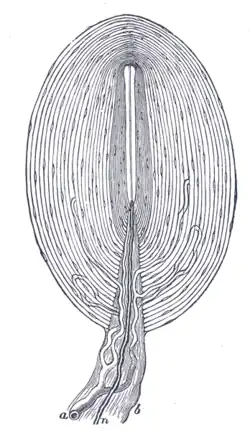

- Receptors for heat, cold, touch, pressure, vibration and pain

Nerves

Sweat glands include the apocrine gland which may act as a sex attractant also opens in to the hair follicle. Eccerine gland which control body temperture.